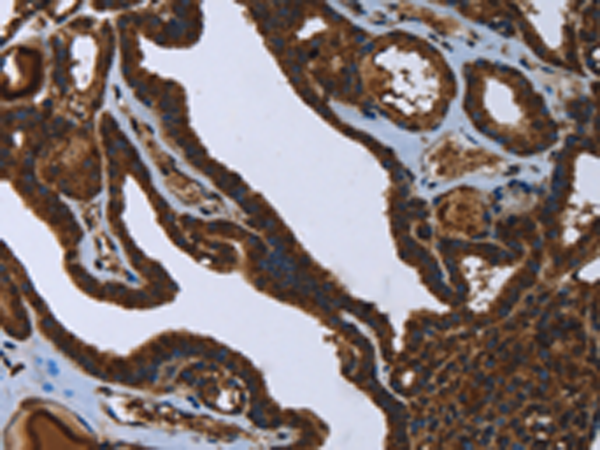

分类: 科研抗体货号: P08301别名: AMDD应用: IHC反应种属: Human